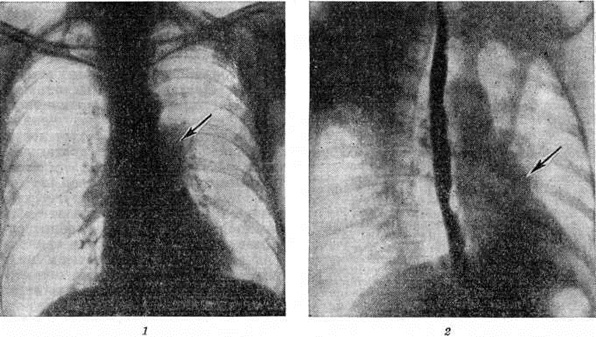

Рис. 4.

Рентгенограммы органов грудной полости больного с хроническим лёгочным сердцем в прямой (1) и правой косой (2) проекциях: сердце имеет относительно небольшие размеры, дуга лёгочного конуса (указана стрелкой) выбухает, корни расширены за счёт крупных ветвей лёгочной артерии, периферический сосудистый рисунок лёгких обеднён.

Рентгенодиагностика. Рентгенологические картина при Лёгочное сердце вариабельна и зависит от стадии и характера лёгочного заболевания. В начальных стадиях развития Лёгочное сердце у больных с выраженной эмфиземой лёгких при рентгеноскопии и рентгенографии в прямой и косых проекциях отмечаются относительно небольшие размеры сердца. Возможны признаки гипертрофии путей оттока от правого желудочка: выбухание лёгочного конуса в прямой и правой косой проекциях (рисунок 4), в выраженных случаях выступающая по левому контуру вторая дуга лёгочного конуса может имитировать «митральную» конфигурацию сердца.

Расширение лёгочного ствола и лёгочных артерий часто сочетается с сужением более мелких их разветвлений (симптом «ампутации» корня) и обеднением периферического сосудистого рисунка лёгких (рисунок 4). Это особенно отчётливо обнаруживается на томограммах и зонограммах лёгких.